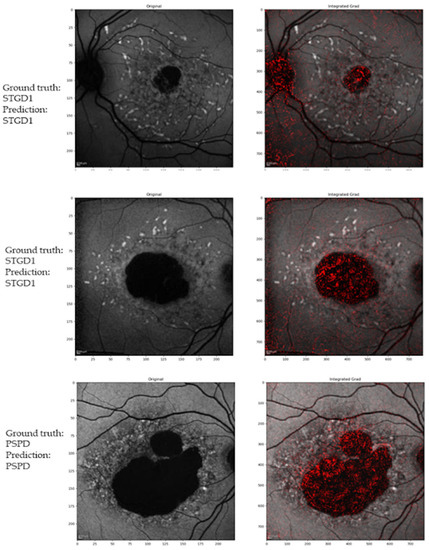

3.1. Deep Learning Classifier